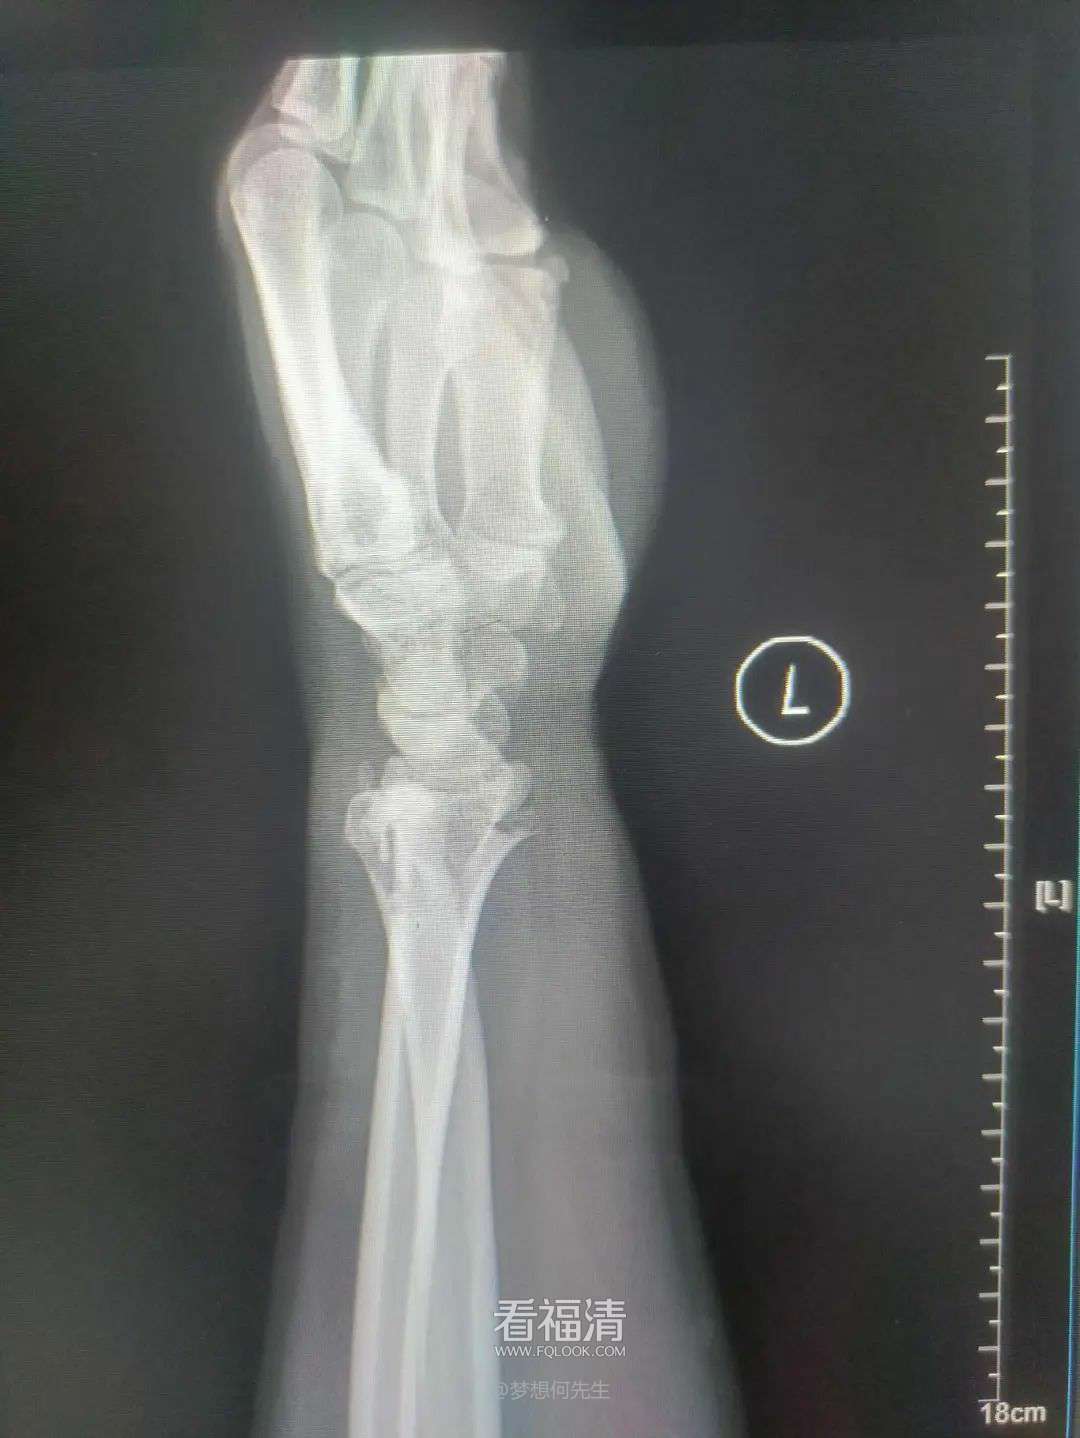

一名年仅12岁的男孩不慎从约一米高的地方跌落,导致左前臂严重受伤,出现畸形、肿痛,并限制了其正常活动。家人急忙带他到福清市第五医院寻求治疗。

复位前

经过细致的影像学检查得知,男孩的左尺桡骨中段不幸遭遇了双骨折。经过全面的病情评估后,王征勇决定运用中医传统的正骨手法为这位小患者进行骨折复位治疗。

在王征勇精湛的手法下,骨折得到了成功的复位。随后的复查影像资料显示,骨断端对位对线良好,完全符合保守治疗的指征。

复位后

为了确保骨折部位的稳定,王征勇为患者精心选择了小夹板联合石膏的混合外固定方案;同时,详细地指导患者进行适当的功能锻炼,加速康复进程。

经过一个月的治疗与康复,患者再次接受影像学检查,结果显示骨折块贴合紧密,愈合情况良好。这让医护团队倍感欣慰。基于这一积极进展,王征勇进一步指导患者开展腕、肘关节的功能锻炼,以帮助他恢复关节的活动范围。在伤后六周的时间里,患者恢复得相当出色,不仅摆脱了伤痛的困扰,还重新找回了往日的活力。